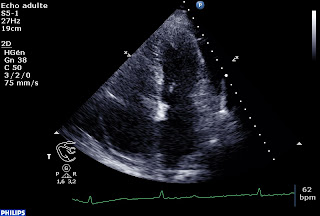

Lui entre en cardiologie pour un flutter auriculaire paucisymptomatique. Antécédents de BPCO post tabagique, pas de « passé cardiologique ». Après CEE, retour en rythme sinusal mais survenue d’une hypotension avec désaturation prolongée. Radio thorax d’OAP, insuffisance rénale sévère et cytolyse majeure sur le premier bilan. Voici l’echographie cardiaque faite au lit en USIC à son retour:

-Épanchement perciardique circonférentiel, non compressif, de 10-12 mm au maximum, par ailleurs déjà noté sur une échographie réalisée 6 mois auparavant pour exploration d’une cytolyse.

-En TM en sous costal, à droite et à gauche de l’écran, on peut voir la courbure septale s’inverser avec un VD qui refoule le septum inter ventriculaire vers les cavités gauches.